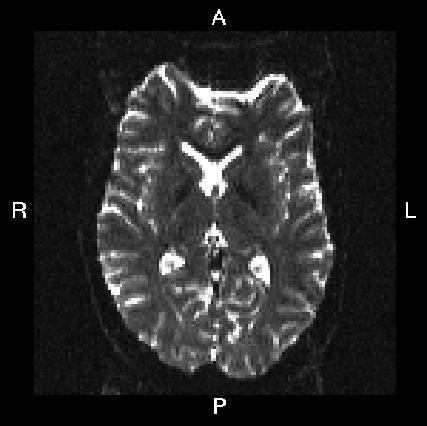

Below you see four examples of images acquired with different phase encoding. Below the images you see what you would find in the PDF protocol generated on a Siemens scanner for these acquisitions. Unfortunately I don't have enough experience of other scanner manufacturers to know where to find the information from those.

If you are uncertain about how to create your own --acqp file I suggest you get your scanner protocol, load your images into FSLVIEW and then find which of the images below that looks most like then one you have. When you have done that compare the "Phase enc." entry below that image with that in your protocol. When you are happy that you have found the right column you can use the three first values from the vector below the image.

| What you see in FSLeyes |

|---|---|---|---|---|

Phase enc. dir A >> P Echo spacing 0.75 ms EPI factor 128 |

| In --acqp file | 0 1 0 0.095 | 0 -1 0 0.095 | 1 0 0 0.122 | -1 0 0 0.122 |